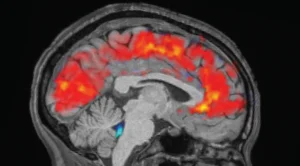

في الصباح، قاس الباحثون ما حدث في أدمغة المشاركين باستخدام قبعات تخطيط كهربية الدماغ (EEG) على المشاركين لتسجيل موجات أدمغتهم عبر أقطاب كهربائية. وفي الوقت نفسه، خضع المشاركون للتصوير بالرنين المغناطيسي الوظيفي (fMRI) للكشف عن أنماط تدفق الدم والسائل الدماغي الشوكي في الدماغ.

وقاست أجهزة تتبع تغير حجم حدقات المشاركين عند شعورهم بالتعب أو النعاس. وبالتالي، تمكن الباحثون من تسجيل موجات الدماغ، وتدفق الدم، وتدفق السائل الدماغي الشوكي، وتغيرات حجم حدقة العين في الوقت نفسه – كما لو كانوا يشاهدون جميع “أنظمة” الدماغ تعمل معًا. وخضع المشاركون أيضًا للتصوير بالرنين المغناطيسي الوظيفي (fMRI) للكشف عن أنماط تدفق الدم والسائل الدماغي الشوكي في الدماغ. وقاست أجهزة تتبع حركة العين حجم حدقة العين لدى المشاركين.